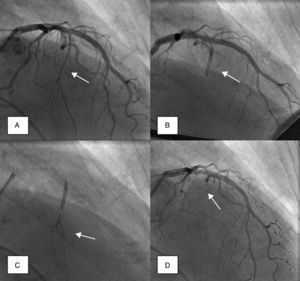

Coronary angiography was then performed to exclude severe coronary disease and to locate the first septal perforator artery. A 0.014-in. guidewire was advanced to engage, in most cases, the first septal branch of the left anterior descending artery (Figure 1A). A slightly oversized, short (∼10mm), over-the-wire angioplasty balloon was then introduced into the septal perforator artery, using standard methods; the lumen of this device provides the route for selective delivery of angiographic contrast, echo contrast, and ultimately alcohol, into the septal artery. After careful fluoroscopic positioning of the balloon (using selective angiography to exclude encroachment onto the LAD), it was inflated and the guidewire removed (Figure 1B).

Angiographic demonstration of alcohol septal ablation technique. Left coronary angiography shows the target septal branch (arrow); an angioplasty guidewire is already inserted inside the septal branch (A). Optimal positioning of the balloon catheter (arrow) in the proximal part of the septal artery without compromise of the left anterior descending artery (B). Injection of angiographic contrast dye through the central lumen of the inflated balloon catheter (arrow) determines the supply area of the septal branch and excludes leakage into the left anterior descending artery or other coronary vessels (C). Final demonstration of the septal artery stump (arrow) after alcohol-induced occlusion (D).

A small amount of angiographic contrast was then injected through the balloon lumen to ensure that there was no spill-back into the LAD or collateral recruitment (Figure 1C). The balloon should not be placed too distally as this may result in a smaller (and solely right-sided) septal infarct, with a consequent reduction in the effect on the outflow gradient. Subsequently, an echocardiographic contrast agent (∼1ml SonoVue, Bracco, Geneva, Switzerland) was injected through the balloon, and the myocardium supplied by the septal artery localized with transthoracic echocardiography (Figure 2). The optimal location within the septum is the point of contact between the anterior mitral valve leaflet and septum in apical four-chamber view. If echocardiographic localization was supportive (no contrast seen outside the thickened basal septum), ablation could proceed. The transvenous pacing wire was re-checked, and intravenous analgesia administered, as the alcohol can cause intense but transient discomfort.

Absolute alcohol (1–3ml) was then administered slowly through the lumen of the balloon, for 3–5 minutes, followed by saline flush under continuous hemodynamic and ECG surveillance. The invasive and echocardiographic gradients were reassessed, a successful procedure being defined as a residual invasive LVOT pressure gradient of less than 50% of baseline value. If the target reduction in pressure gradient was not achieved, alcohol injection was repeated after 5 minutes (1–2ml) within the same perforator branch. If not successful, the procedure was repeated in a second perforator branch. Once success was achieved, the balloon was deflated, and coronary angiography was repeated to confirm the occlusion of the septal branch and the patency of the left anterior descending coronary artery (Figure 1D). Following deflation, the balloon and wire were removed.